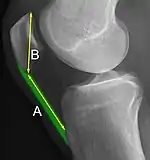

A patella alta is a high-riding (superiorly aligned) patella. An attenuated patella alta is an unusually small patella that develops out of and above the joint.

A patella baja is a low-riding patella. A long-standing patella baja may result in extensor dysfunction.[5]

The Insall-Salvati ratio helps to indicate patella baja on lateral X-rays, and is calculated as the patellar tendon length divided by the patellar bone length. An Insall-Salvati ratio of < 0.8 indicates patella baja.[6]